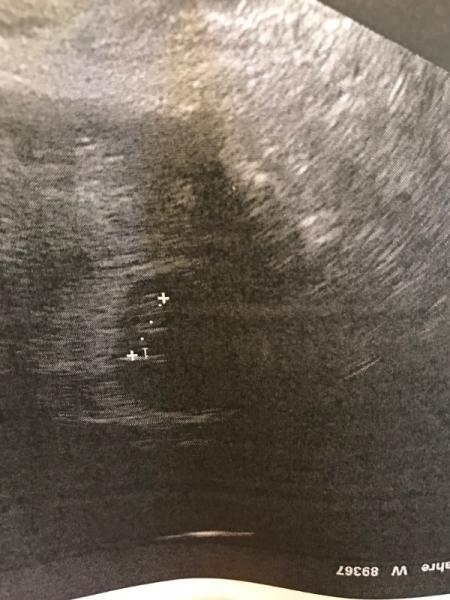

Huhu. Ich bin erstmal ziemlich erleichtert! Ich habe absolut nichts an Symptomen. Mir geht es so gut, dass ich manchmal glatt vergesse, dass ich schwanger bin. Nach 3 Fehlgeburten habe ich heute bei 7+0 einen kleinen Wurm von 1cm mit Herzschlag gesehen. Jetzt heißt es weiter beten, dass es diesmal auch bei uns bleibt!

Bild zu Arzttermin - Forum für Januar - Mamis